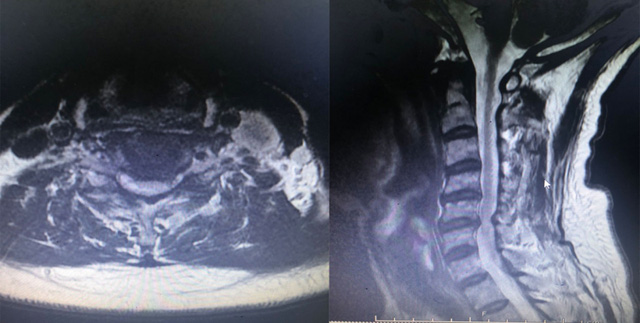

Hình ảnh MRI tổn thương cột sống cổ của người bệnh

Bệnh nhân Nguyễn M H (65 tuổi, trú tại TP Hạ Long, Quảng Ninh) bị tai nạn giao thông được chuyển đến Bệnh viện Bãi Cháy trong tình trạng mất vận động hai chi dưới, gãy xương tay phải, tứ chi tê bì, bí đại, tiểu tiện. Hình ảnh chụp MRI cho thấy phù tủy cổ ngang mức đĩa đệm C5/6; phình thoát vị đĩa đệm C3/4, C5/6 gây chèn ép rễ thần kinh ngang mức, thoái hóa đa tầng đĩa đệm và cột sống cổ. Các bác sĩ đã hội chẩn chuyên khoa Ngoại thần kinh cột sống và chỉ định thực hiện phẫu thuật ACDF cố định cột sống cổ, thay đĩa đệm cột sống cổ, hàn xương lối trước dưới sự hộ trợ của kính vi phẫu thế hệ mới nhằm giải phóng hẹp ống sống, chèn ép rễ thần kinh cột sống cổ, cải thiện chất lượng vận động cho người bệnh. "Phẫu thuật ACDF là phẫu thuật có độ khó cao đòi hỏi phẫu thuật viên phải được đào tạo bài bản, trang thiết bị phòng mổ hiện đại. Đặc biệt, việc ứng dụng kính vi phẫu cho hình ảnh phóng đại rõ nét trong phẫu thuật ACDF giúp các phẫu thuật viên quan sát tốt trường giải phẫu, lấy đĩa đệm bị tổn thương, hàn, ghép xương mào chậu hoặc xương sinh học vào khoảng trống sau khi lấy đĩa đệm để định hình cột sống cổ thuận lợi hơn, kiểm soát tốt các tai biến, nẹp vít cố định chính xác giúp hạn chế hiện tượng lỏng, xô nẹp khi bệnh nhân vận động cổ." – Bác sĩ CKI Lê Triệu Linh (Khoa Ngoại Thần kinh sọ não, cột sống, Bệnh viện Bãi Cháy) cho biết. Ca phẫu thuật do ekip bác sĩ CKI Lê Triệu Linh, bác sĩ nội trú Khúc Văn Trung thực hiện diễn ra thành công. Sau phẫu thuật 7 ngày, các triệu chứng tê bì tứ chi của bệnh nhân được cải thiện, có thể vận động tay chân khoảng 60% so với trước phẫu thuật, bệnh nhân có thể tự chủ đại tiểu tiện. Bệnh nhân tiếp tục được tập phục hồi chức năng sau phẫu thuật để cải thiện vận động. Đến nay, bệnh nhân có thể đạp xe, đi lại được tốt hơn.